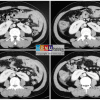

V. Chẩn đoán UIV / CT

– Hai thận xoay trục, cực dưới hướng vào trong phía cột sống.

– Đài bể thận bình thường hướng lên trên ra ngoài => hướng xuống dưới.

– Phần nối hai cực dưới là nhu mô hoặc dải xơ vắt ngang phía trước cột sống.

=> Case lâm sàng 1:

=> Case lâm sàng 2: